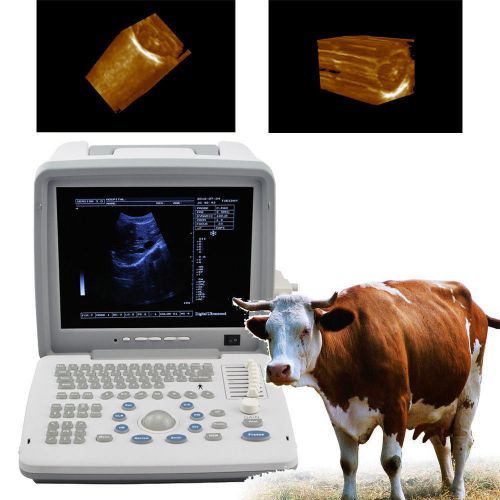

3D Portable Notebook Digital Laptop Ultrasound machine Scanner CONVEX PROBE

12.1 Veterinary VET Full Digital Portable Ultrasound Scanner linear 3D software

New 12.1 Full Digital Portable Ultrasound Scanner trans vaginal 3D workstation

3D Full Digital Portable Ultrasound Scanner convex & Transvaginal 3D workstation

12.1 LED Full Digital Portable Ultrasound Scanner rectal probe 3D workstation CE

Veterinary vet Full Digital Portable Ultrasound Scanner Rectal 3D workstation

2014 Veterinary vet Full Digital Portable Ultrasound Scanner Rectal 3D Software

NEW Diagnostic Ultrasound Scanner MACHINE +3D function + convex sensor pregnancy

2015 Digital Laptop Ultrasound Scanner+Convex+ Transvaginal Probe+ 3D image-DHL